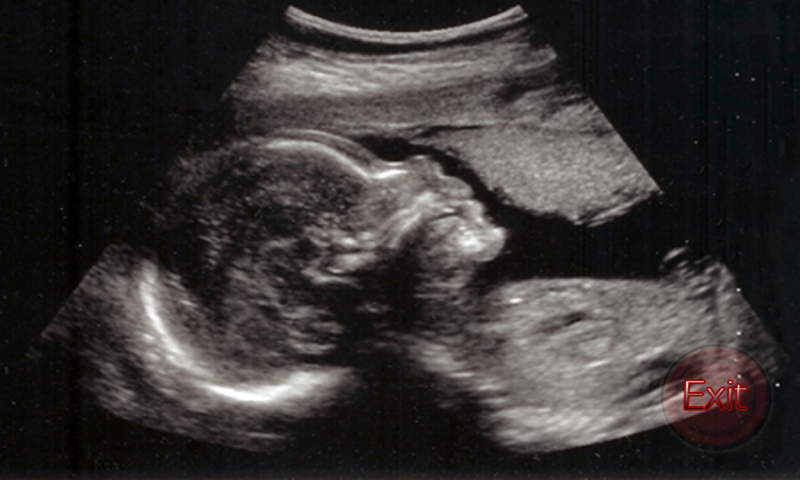

1 Ultrasound in Pregnancy An ultrasound is a test that uses sound waves to look at your baby, the uterus and the placenta. You will be able to hear your baby’s heartbeat ... Read Document

Ruch Clinic Pregnancy Guide ! Ultrasound during Pregnancy In obstetrics, ultrasound is used to exam the growing fetus inside the mother’s uterus. ... Get Doc

Ultrasound is a type of sound with a frequency bigger than humans can hear. Obstetric sonography is commonly used during pregnancy. Ultrasound is generally thought of as a "safe test" because it does not use ionising (destructive) ... Read Article

Maternity: Pregnancy Ultrasound - YouTube